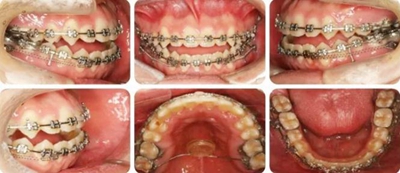

6個(gè)月,上牙列擁擠得到解除。上下頜植入種植釘,用于上后牙壓低及下牙列遠(yuǎn)移。

14個(gè)月,前牙開頜得到改善,配合使用垂直牽引。

16個(gè)月,前牙開頜糾正。

結(jié)束時(shí),可見前牙覆合覆蓋正常,上下牙列排齊,雙側(cè)尖磨牙達(dá)到中性關(guān)系。

高角反頜伴開頜病例,多采用正畸正頜聯(lián)合治療。但該患者為直面型,下牙列輕度擁擠,下前牙直立,且年齡較小,手術(shù)治療非首選。采用種植釘內(nèi)收下前牙代償性治療前牙反合。而且需要拔除阻生智齒減小遠(yuǎn)移下牙列的阻力。

羅晨醫(yī)生:我今天展示的病例,技術(shù)創(chuàng)新在于種植釘整體遠(yuǎn)移下頜全牙列。臨床正畸治療中,對(duì)于反頜伴開頜的患者,一直是令人困擾的難題。以往的上頜骨嚴(yán)重發(fā)育不足的患者,只能通過正頜手術(shù)進(jìn)行改善,但一來患者比較痛苦,二來費(fèi)用較高,

給患者帶來很大的負(fù)擔(dān)。而本病例通過下頜頰棚區(qū)植入微種植釘,整體將下頜牙列內(nèi)收,引起下頜骨逆時(shí)針旋轉(zhuǎn),開合和反合得到了糾正,達(dá)到了良好的效果。